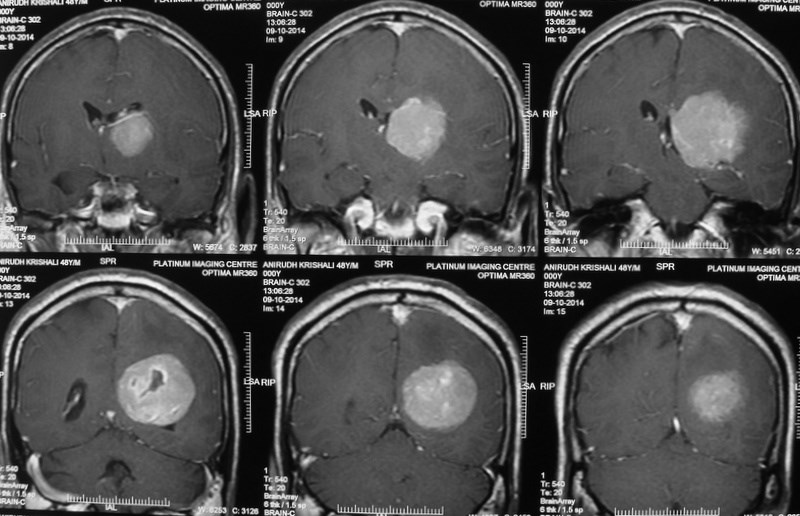

Intracranial Meningiomas

Meningiomas are solid, nodular (rarely, cystic), benign tumors that arise from the coverings of the brain, and compress the adjacent brain tissue. Usually present with headache, visual disturbances or weakness of half of the body. Diagnosis is by progression, especially if the tumor removal has been incomplete. Diagnosis is by MRI and surgery is curative.

Intraventricular Meningiomas

Meningiomas that occur within the ventricular cavities of the brain constitute a special group, and need special surgical planning to safeguard the vital areas of the brain.